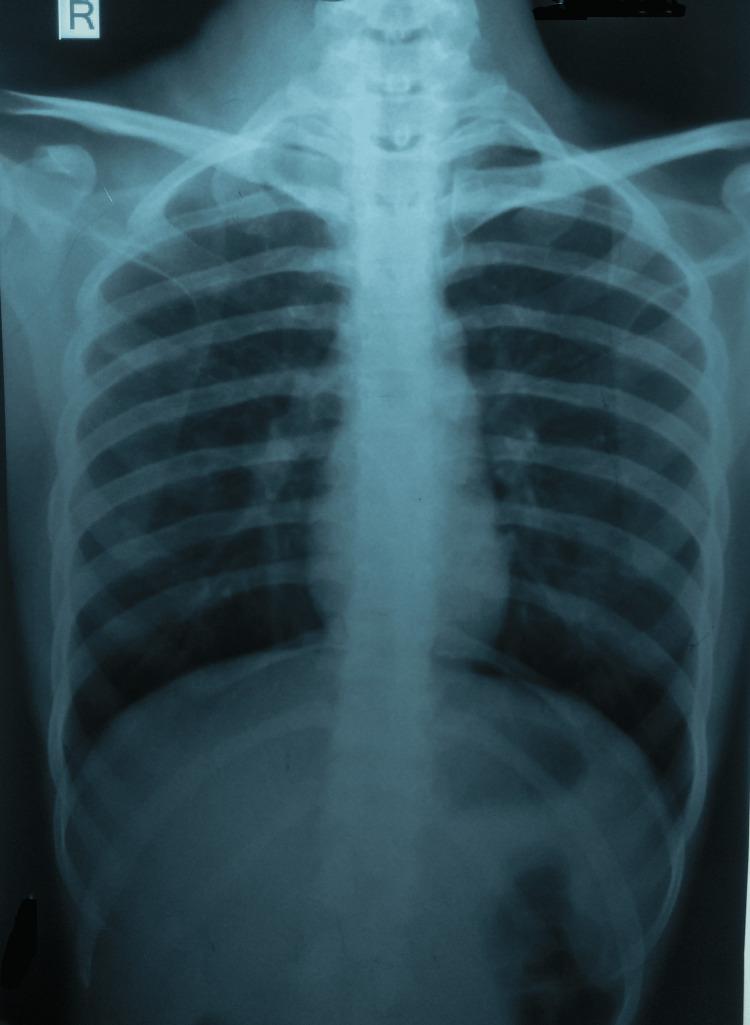

In clinical settings, cutaneous tuberculosis is an uncommon occurrence. On the other hand, incidences of this kind of tuberculosis are usually documented in high-burden nations. Despite being the most prevalent variety of cutaneous tuberculosis, scrofuloderma frequently goes undiagnosed. The present case is a rare case of simultaneous involvement of cervical, supraclavicular, and pretracheal lymph nodes and skin due to . A 26-year-old Indian female was diagnosed after a careful diagnostic workup involving fine needle aspiration cytology, a cartridge-based nucleic acid amplification test, and a biopsy. The case is remarkable as there was no pulmonary involvement. She was initiated on antitubercular treatment per national policy.

在临床环境中,皮肤结核并不常见。另一方面,这种结核病的发病率通常在高负担国家有记录。尽管瘰疬性皮肤结核是最常见的皮肤结核类型,但它经常未被诊断出来。本病例是一例罕见的因……同时累及颈部、锁骨上和气管前淋巴结及皮肤的病例。一名26岁的印度女性在经过包括细针穿刺细胞学检查、基于 cartridge 的核酸扩增试验和活检在内的仔细诊断检查后被确诊。该病例值得注意的是没有肺部受累。她根据国家政策开始接受抗结核治疗。